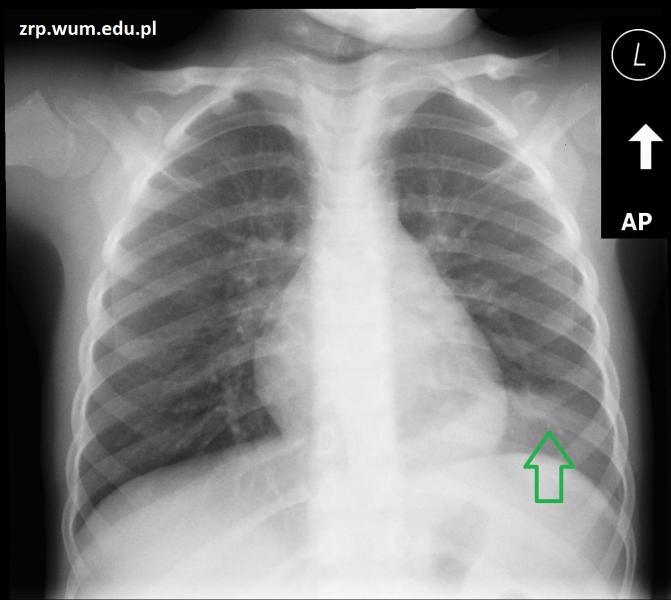

Przypadek 27: 5-letni pacjent zgłosił się do IP z powodu gorączki i bólu brzucha.

Rozpoznanie potwierdzono w badaniu RTG klatki piersiowej - zagęszczenia miąższowe w nadprzeponowej części płuca lewego, od tyłu (zielona strzałka).